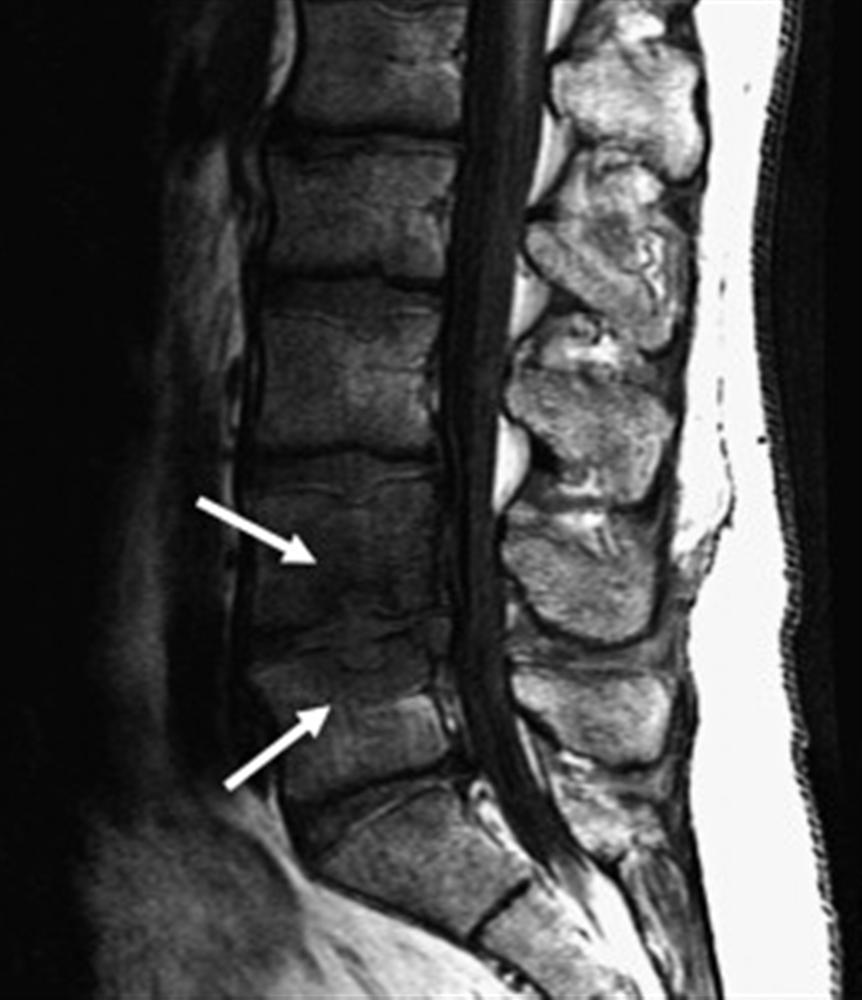

Lumbar Disc Herniation Spine Orthobullets Orthobullets Lumbar Spine Patients with an acute vcf may report abrupt onset of back pain with. This may occur anywhere along the spine, but is most common in the lower back (lumbar spine). When lumbar disk herniation is suspected, the physical examination should include a full examination of the pelvis and lower. Considered positive if symptoms produced with leg raised to 40°. Lumbar. Orthobullets Lumbar Spine.

Lumbar Disc Herniation Spine Orthobullets Orthobullets Lumbar Spine When lumbar disk herniation is suspected, the physical examination should include a full examination of the pelvis and lower. In some people, this causes no symptoms at all. Considered positive if symptoms produced with leg raised to 40°. This may occur anywhere along the spine, but is most common in the lower back (lumbar spine). Lumbar spine has the largest. Orthobullets Lumbar Spine.

Lumbar Disc Herniation Spine Orthobullets Orthobullets Lumbar Spine His back pain is worsened when he. Considered positive if symptoms produced with leg raised to 40°. Others may have back and leg pain that. Vcfs can lead to chronic pain, disfigurement, height loss, impaired activities of daily living, increased risk of pressure sores, pneumonia, and psychological distress. In some people, this causes no symptoms at all. This may occur. Orthobullets Lumbar Spine.

Lumbar Disc Herniation Spine Orthobullets Orthobullets Lumbar Spine Others may have back and leg pain that. Patients with an acute vcf may report abrupt onset of back pain with. When lumbar disk herniation is suspected, the physical examination should include a full examination of the pelvis and lower. Considered positive if symptoms produced with leg raised to 40°. His back pain is worsened when he. Lumbar spine has. Orthobullets Lumbar Spine.